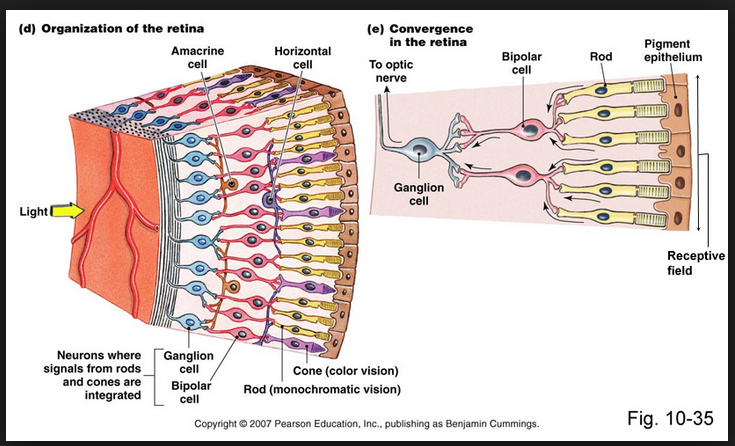

44 eye cones/rods software wars

45 Father Brown TV and uranium 92 protons